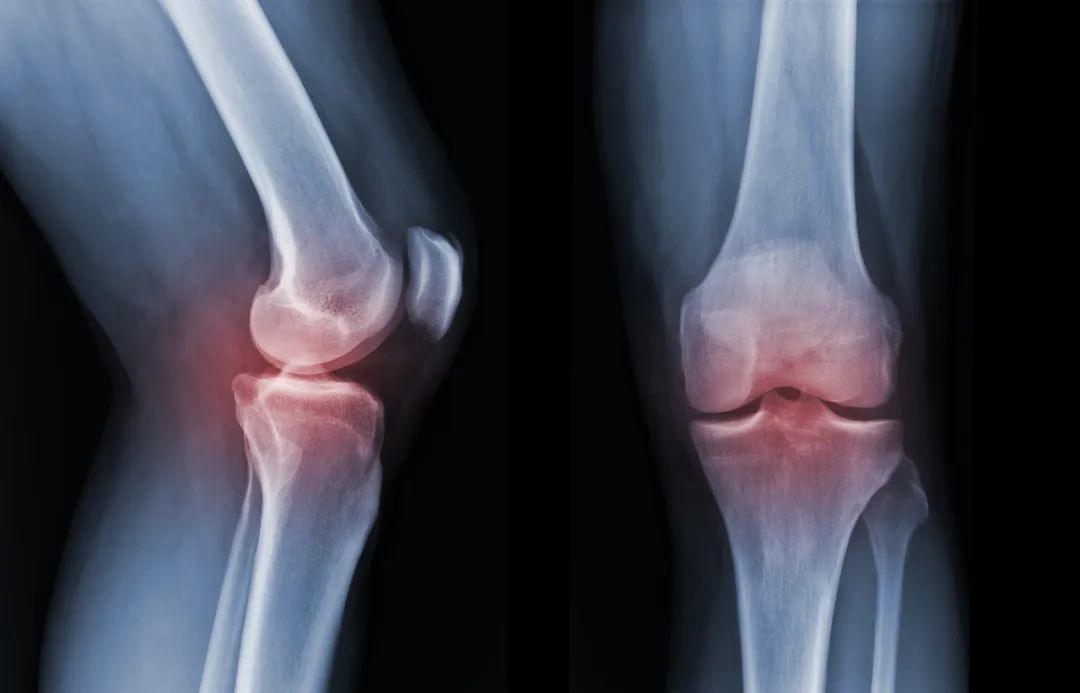

图片来源:摄图网

4.X线检查

X线是常规的骨科检查方法,但X线并不作为骨转移的常规检查手段,而是常用于对有临床症状的部位(如:疼痛、病理骨折)或其他影像学检查(如:ECT或MRI)所发现的异常进行补充评估。

优点: X线检查主要用来观察骨病变的全貌, 病程的进展和手术后的复查;

缺点: 检测早期骨转移瘤的灵敏度低,难以发现早期转移灶。